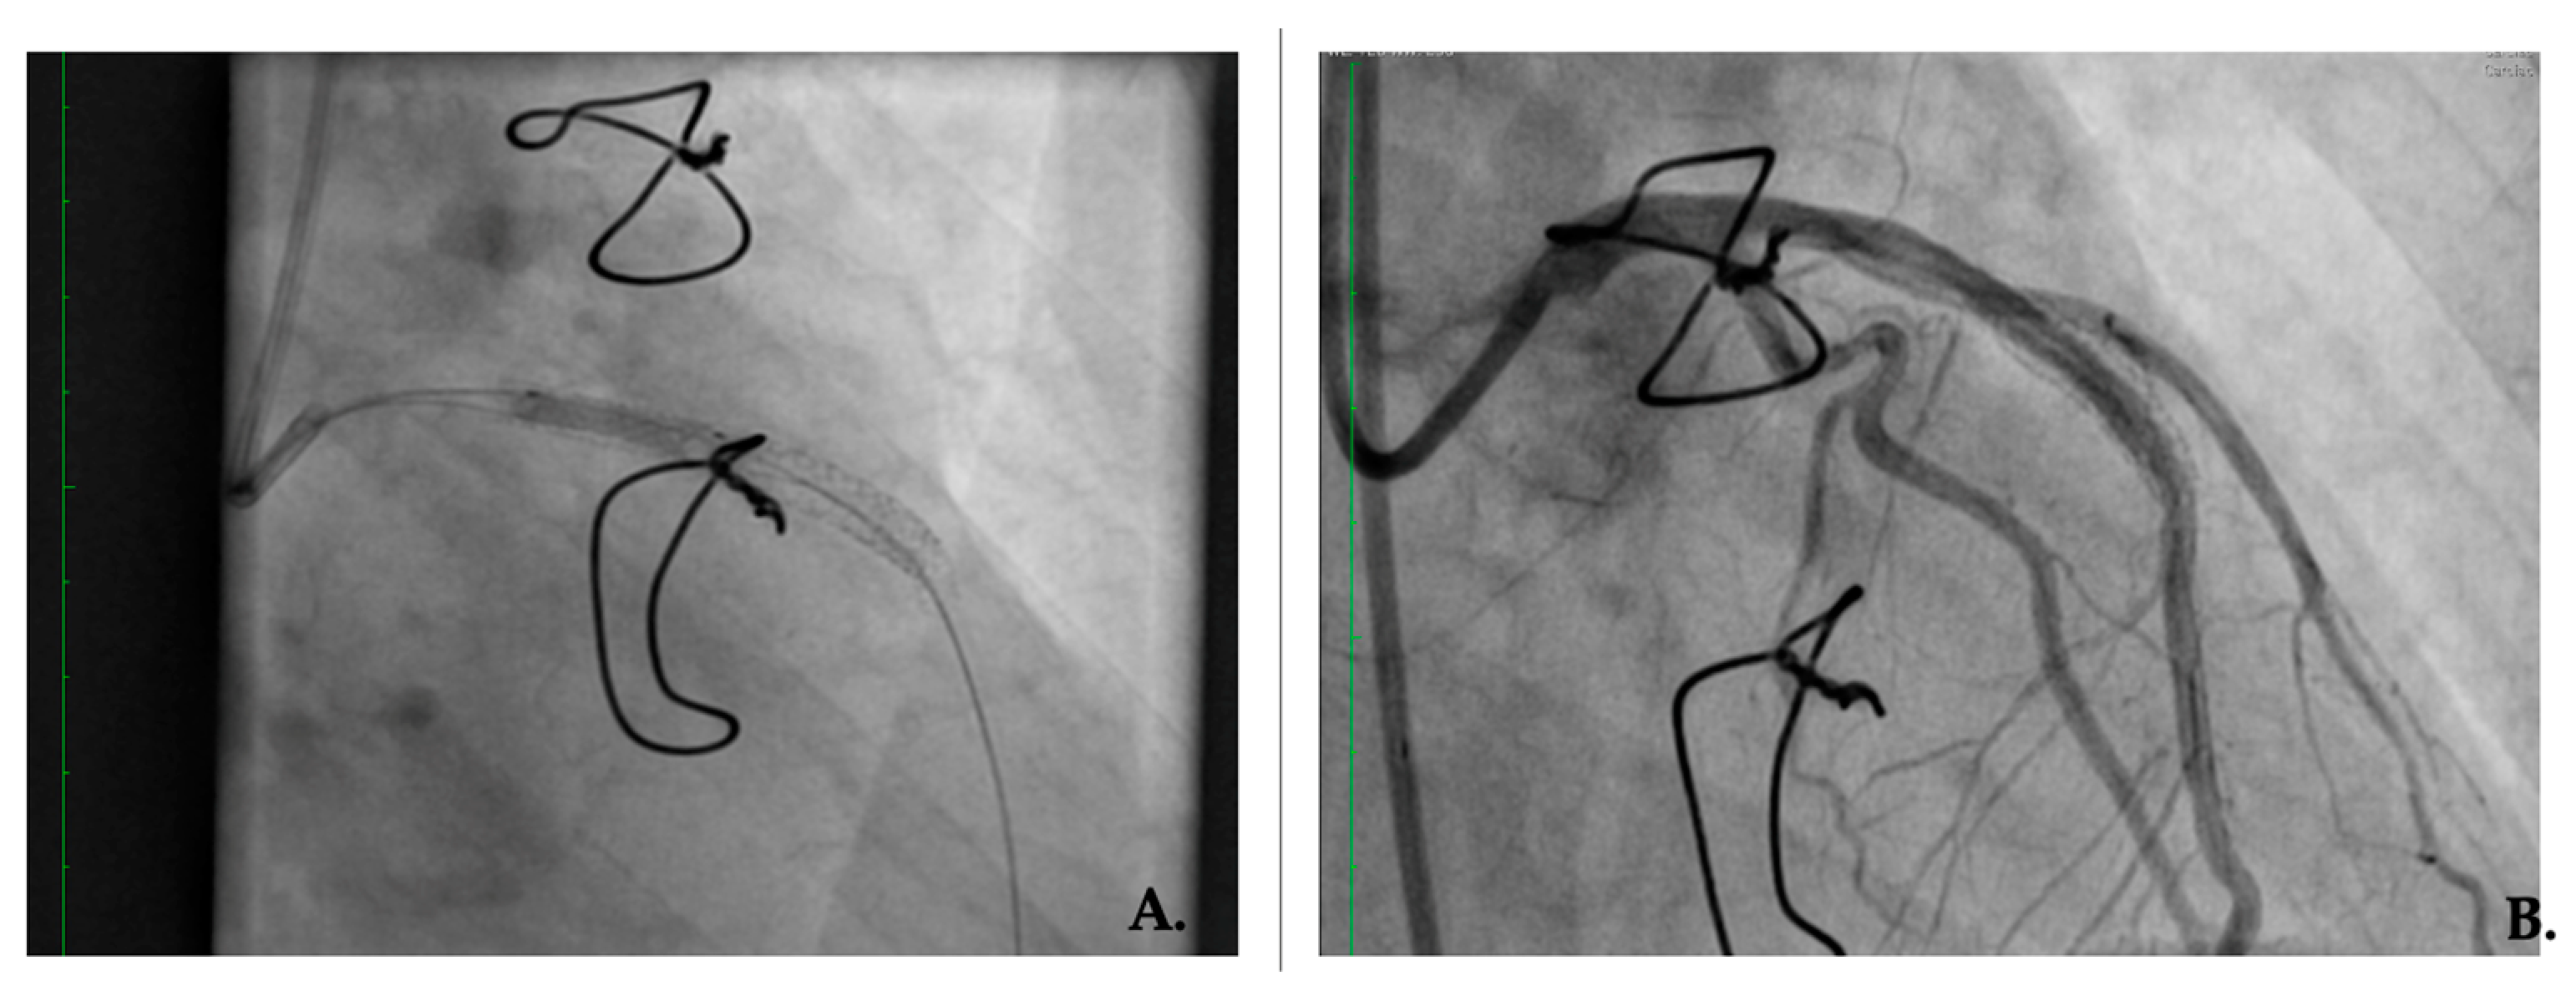

Figure 2.

First patient restenosis treated with a drug-eluting stent in a bare-metal stent (A) Drug-eluting stent implantation after bare-metal stent restenosis. (B) Right anterior oblique cranial angulation view: in-stent restenosis on the descending anterior artery; patent left main and circumflex artery.